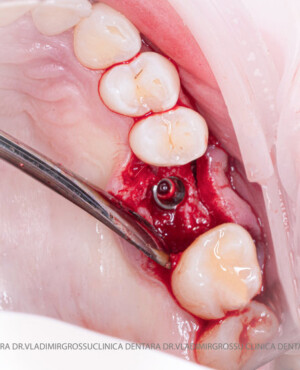

După extracția dentară, în intervalul de 6-12 luni, osul alveolar suferă un proces natural de remodelare, ceea ce conduce la scăderea volumului osos prin rezorbție. De aceea, inserția implantului dentar este ideală imediat după extracție sau, cel târziu, în primele 3-4 luni după aceasta.Scopul procedurilor de adiție osoasă este refacerea fundației osoase necesare pentru stabilizarea corectă a implantului dentar. Pentru ca un implant să reziste în timp la forțele masticatorii, este nevoie de o bază osoasă solidă și sănătoasă.

Procesul de refacere osoasă este complex, însă, simplificat, se bazează pe faptul că osul adăugat se integrează treptat, fiind înlocuit parțial cu os natural, oferind astfel suportul necesar implantului.

Un element esențial în procedura de aditie osoasă este utilizarea membranelor biologice, care izolează materialul osos de țesuturile moi (gingie) pe durata procesului de vindecare. Cele mai recomandate sunt membranele resorbabile din colagen sau pericard.

Adiția osoasă are un rol crucial pentru poziționarea corectă și stabilă a implanturilor dentare. Clinica stomatologică Dr. Grossu din Chișinău promovează o abordare chirurgicală estetică și predictibilă, adaptată fiecărui caz în parte.